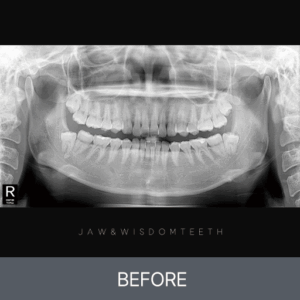

사랑니 CASE